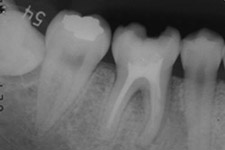

適切な条件がそろえば、歯の移植が可能です。歯の移植とは、治療することができない歯を抜いて、その場所へ本人の親知らずなどの歯を移す治療です。例えば、下のパノラマエックス線写真は18歳の男子です。右下の第一大臼歯が割れて痛みを伴って来院されました。この歯の保存できないと判断して、その歯を抜歯し,後ろにあるまだ生えていない親知らずをそこへ移植しました。移植の適切な条件とは、患者さん年齢が概ね40歳以下であること、口腔内に適切なドナー歯(主に親知らず)があること、移植歯(ドナー歯)と移植部位(受容側)の大きさが適合すること、などです。

治療前:第一大臼歯が割れてしまっていて治療することが困難です。

第一大臼歯の抜歯後2週間で移植を行いました。

移植のために抜歯された右下の親知らず。歯根がまだ完成していない若い歯です。

移植直後

移植直後。歯根がまだ完成していない歯では、根の先が開いていることに気づきます。

移植後4年。親知らずが第一大臼歯の代わりを担っています。

4年後。移植後に根が少し成長しているのが分かります。歯の神経もつながっています。